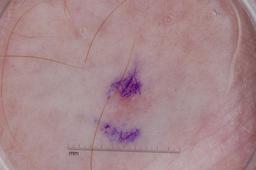

MSK-4

- Name: MSK-4

Description:

Images found based on a search for patients with a personal history, clinical diagnosis, or differential diagnosis of melanoma. All diagnoses confirmed by histopathology.